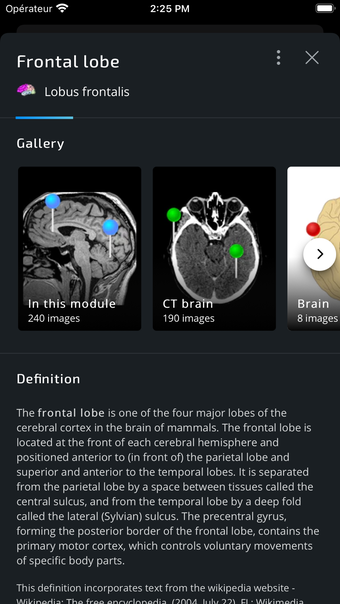

IMAIOS e-Anatomy es un atlas en línea de anatomía humana para médicos, enfermeras, estudiantes de medicina y técnicos en radiología. Utiliza IMAIOS e-Anatomy en tu smartphone o tablet para encontrar la ubicación de cualquier condición médica o estructura anatómica. El detallado e-Anatomy te proporcionará una referencia de acceso rápido de la anatomía humana y sus principales órganos y funciones.

Encuentra la ubicación de cualquier condición médica o estructura anatómica con IMAIOS e-Anatomy en tu smartphone o tablet. Busca enfermedades, anatomía y estructuras anatómicas, e incluso ve la ubicación de todos los puntos de referencia anatómicos. Puedes encontrar la ubicación de cualquier estructura o condición anatómica con la información médica detallada, fácilmente ingresando los detalles anatómicos relevantes.

Encuentra la ubicación de cualquier estructura o condición anatómica con IMAIOS e-Anatomy en tu smartphone o tablet. Utiliza la guía de anatomía para encontrar la ubicación de las estructuras anatómicas, enfermedades y trastornos, e incluso la anatomía y estructura de los dedos y manos.

IMAIOS e-Anatomy es un atlas médico. Utilízalo como referencia médica para averiguar dónde se encuentra cualquier condición médica o estructura anatómica en el cuerpo humano.

IMAIOS e-Anatomy es un atlas en línea de anatomía humana. Proporciona información médica detallada sobre la anatomía y estructura del cuerpo humano. Utiliza IMAIOS e-Anatomy en tu smartphone o tablet para encontrar la ubicación de cualquier estructura o condición anatómica.